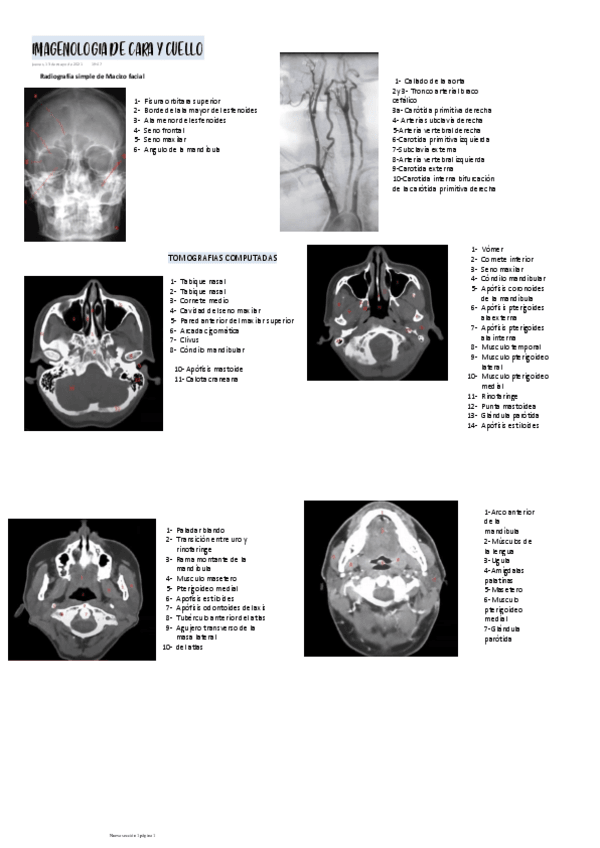

He publicado nuevos apuntes de 1º Medicina Familiar I: IMAGENOLOGIA-DE-CARA-Y-CUELLOO.pdf

3 páginas